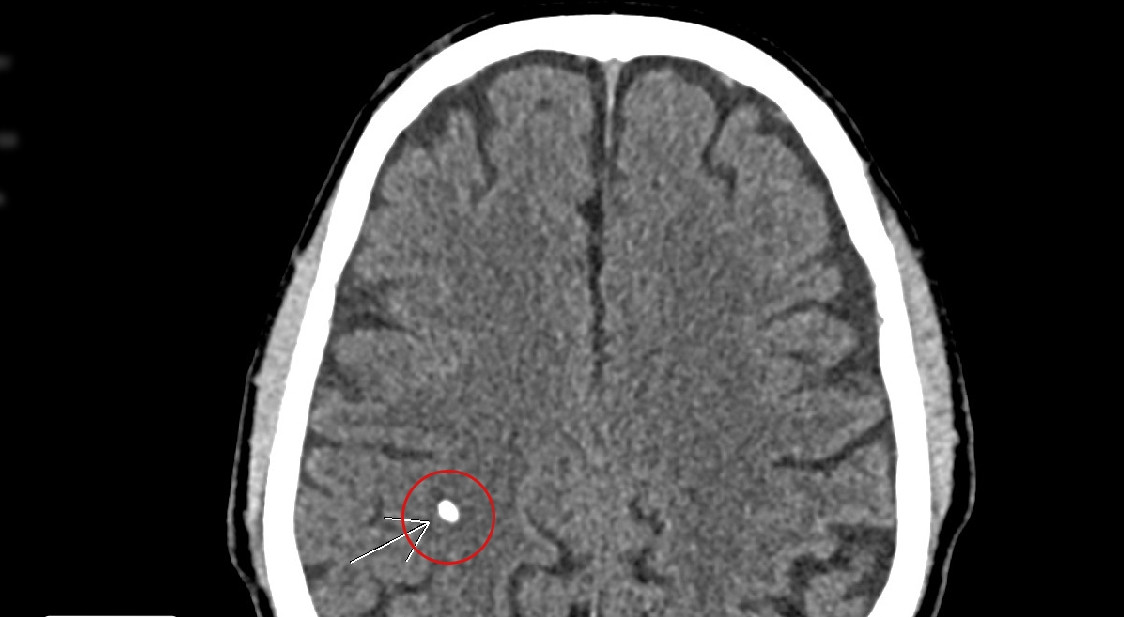

Nhu mô não có hình ảnh rải rác các di chứng ấu trùng sán não, kèm theo tổn thương viêm đa xoang, xơ vữa vôi hoá động mạch cảnh hai bên đoạn xoang hang.